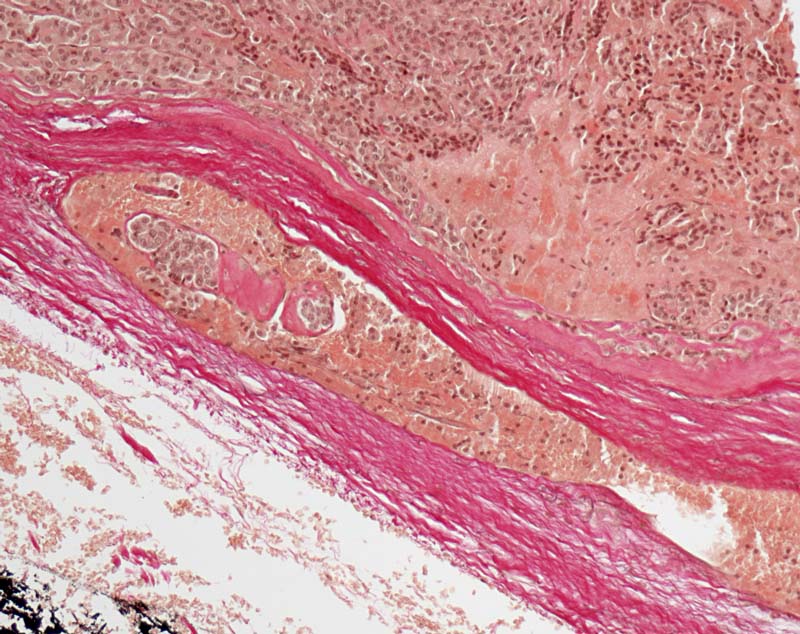

Follikuläres Schilddrüsenkarzinom: Gefässeinbruch

In einem endothelausgekleideten Gefäss der Tumorkapsel ist ein organisierter Tumorthrombus erkennbar.

Als eindeutige Gefässeinbrüche eines Schilddrüsenkarzinoms sind ausschliesslich Tumorthromben oder wandhaftende Tumorzellen in einem Gefäss in oder ausserhalb der Tumorkapsel anzusehen. Während der Verarbeitung des Operationspräparates werden oft einzelne Tumorzellen in Gefässlumina reingewischt. Solche reaktionslos innerhalb des Gefässlumens liegende Tumorzellen gelten nicht als Gefässeinbrüche (siehe Bild 8266).